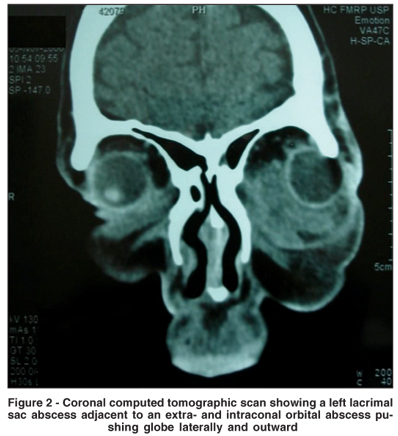

A 39-year-old, otherwise healthy woman presented to the emergency department of the "Hospital Clinicas Faculdade Medicina Ribeirão Preto - Universidade de São Paulo - HCFMRP-USP" with fever and a history of yellowish discharge, eyelid swelling, pain, redness, and reduced vision in the left eye. She reported epiphora in the last six months and denied any sinus disease, periocular trauma or prior infections. She had been using 500 mg oral cephalexin every 6 hours in the last days. Her visual acuity was 20/20 in the right eye and 20/100 in the left. The pupils were equal, with normal reflexes. She presented with a clear abscess on the lower eyelid, with pus drainage occurring upon external pressure. The left eye was proptotic with an important degree of chemosis and extraocular motility limitation (Figure 1). The patient was admitted to the hospital and intravenous therapy was started with 1 g ceftriaxone every 12 hours. Her leukocyte count was 15.6 x 109/L, with 84% segmented neutrophils and 16% lymphocytes. A computed tomography (CT) scan of the orbits showed left proptosis, severe soft tissue edema and intraconal abscesses, with no signs of rhinosinusitis (Figure 2). The patient was submitted to orbital drainage under general anesthesia. The orbit was approached through a subciliary incision. The abscess was located and drained, releasing a large amount of pus. After drainage of the abscess, irrigation of the lacrimal sac through the lower canaliculus clearly demonstrated that the sac was ruptured. The skin was closed and a small Penrose drain was left in the wound. On the third postoperative day the patient was afebrile, with a marked decrease in eyelid swelling and improved ocular motility of the left eye. Culture of the tissues grew strictly anaerobic bacteria (Peptostreptococcus prevotii and Prevotella melaninogenica). After resolution of the infection her final visual acuity was 20/20 in both eyes and an external dacryocystorhinostomy (DCR) was performed.